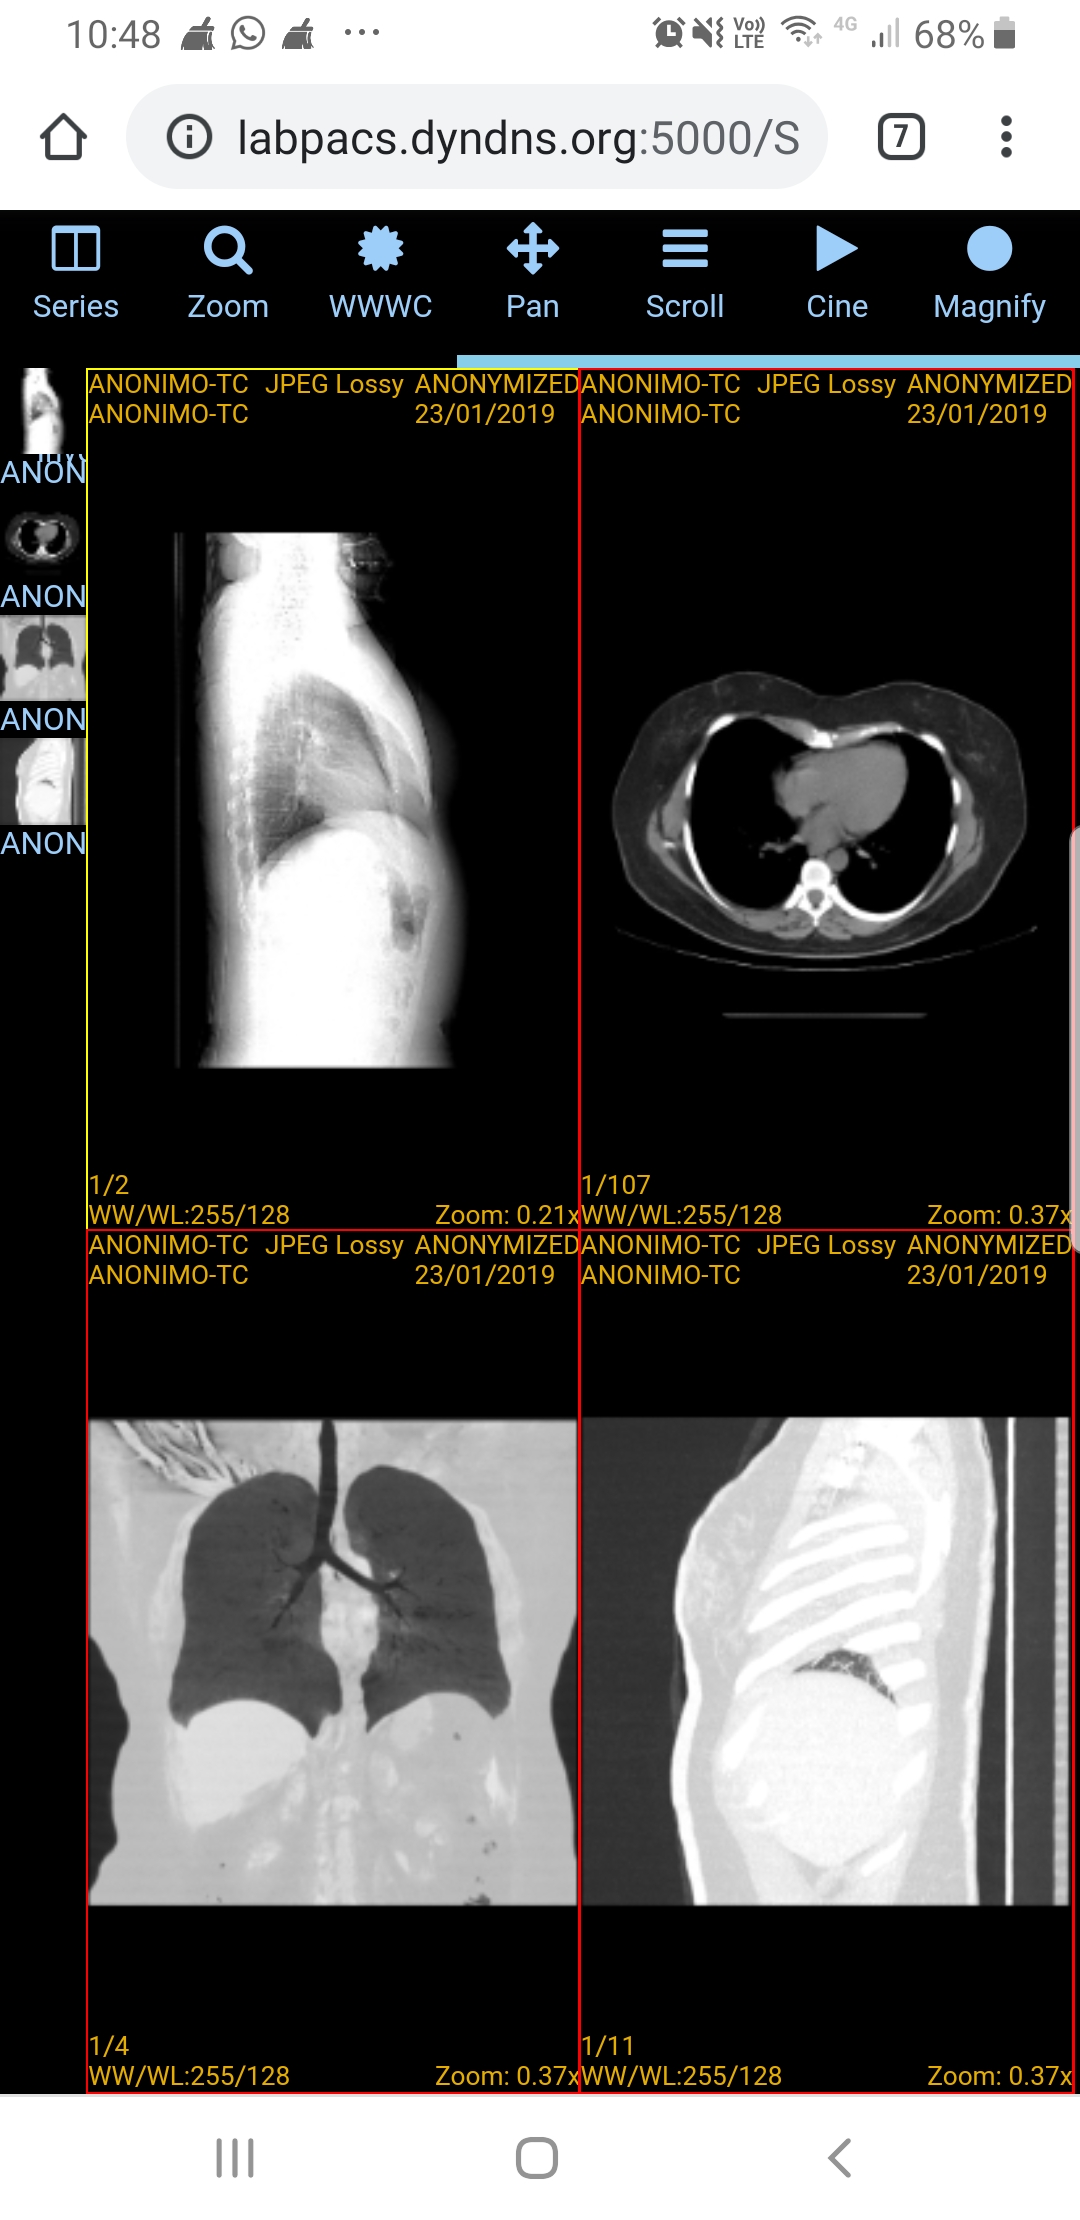

Garantindo transparência e empoderamento do paciente, o app Mobile RES é um aplicativo para celular que permite ao paciente, consultar seus dados clínicos disponibilizados pelo RES, como: indicadores personalizados de saúde; atendimentos na rede de saúde integrada; receituários médicos; alergias; sinais vitais; exames laboratoriais; como também, laudos e visualizadores de exames de imagem.

Além disso, com o app Mobile RES, é possível trocar mensagens com o paciente, informando sobre exames que estão prontos, marcação de consultas e muito mais!